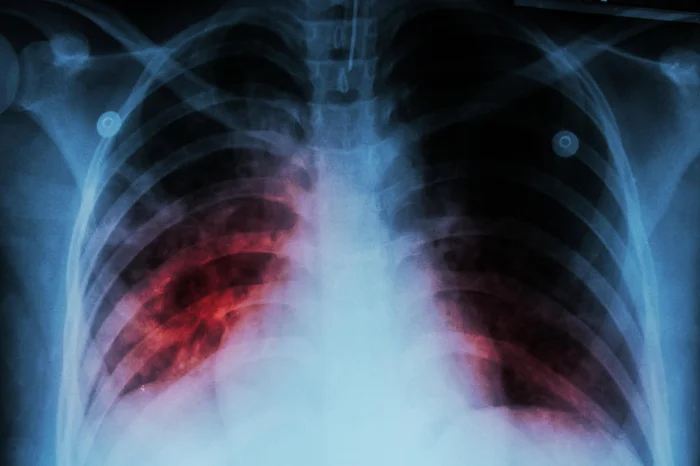

Porto Alegre vai inaugurar, na próxima segunda-feira (13), um novo centro para atendimento de casos de tuberculose e de doenças sexualmente transmissíveis. A estrutura irá funcionar no prédio que antes era usado pelo Ambulatório de Dermatologia Sanitária do Rio Grande do Sul.

No Centro Regionalizado de Atenção Integral e Prevenção às Infecções Sexualmente Transmissíveis (CRAIP) são oferecidos atendimentos especializados para doenças como HIV, Aids e hepatites virais.

O foco é a prevenção, diagnóstico e tratamento dos casos. Também são oferecidas testagem e profilaxias pré e pós-exposição.

O setor referência em tuberculose também contará com uma farmácia e um centro de testagem. Com a nova estrutura, Porto Alegre passa a contar com nove serviços para tratamento de doenças sexualmente transmissíveis.